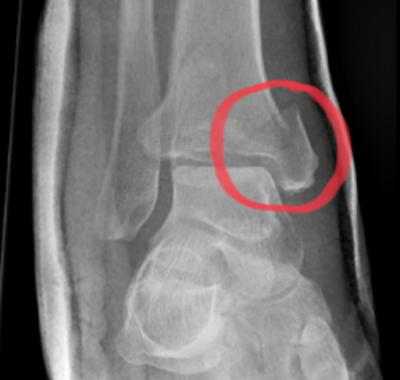

Bij een volledige ruptuur kan beweging in het getroffen gebied vrijwel onmogelijk zijn. Een gedeeltelijke scheur kan minder opvallende klachten geven, maar kan alsnog leiden tot langdurige pijn en functieverlies. Bij een volledige ruptuur kan het nodig zijn dat er een operatie nodig is. Dit moet zo snel mogelijk gebeuren na de ruptuur omdat het lichaam de spier/ pees anders zelf opruimt. Een peesscheur kan worden vastgesteld door lichamelijk onderzoek, een echo of ander beeldvormend onderzoek.